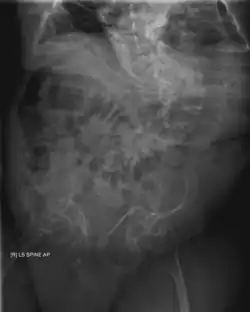

OI—especially its severe form, type III—also has effects on the gastrointestinal system. It was found to be associated with recurrent abdominal pain and chronic constipation in two studies on patients affected by OI.[40][41] Chronic constipation is especially common,[1]: 377 and is thought to be aggravated by an asymmetric pelvis (acetabular protrusion).[1]: 377 [41] Especially in childhood, OI-associated constipation may cause a feeling of fullness and associated food refusal, leading to malnutrition.[1]: 377

OI type III causes osteopenic bones that fracture very easily, sometimes even in utero, often leading to hundreds of fractures during a lifetime;[24] early scoliosis that progresses until puberty; dwarfism (a final adult height frequently less than 4 feet or 120 centimetres); loose joints; and possible respiratory problems due to low rib cage volume causing low lung volumes.[5]: 1512

Diagnosis is typically based on medical imaging, including plain X-rays, and symptoms. In severe OI, signs on medical imaging include abnormalities in all extremities and the spine.[97] As X-rays are often insensitive to the comparatively smaller bone density loss associated with type I OI, DEXA scans may be needed.[5]: 1514

Spinal

Spinal fusion can be performed either as a preventative measure or to correct existing scoliosis, although the inherent fragility of OI bone makes this operation more complex in OI patients than it does with patients who have adolescent idiopathic scoliosis, but normal bone density.[121] Despite the risks, however, three Nemours–duPont orthopedic surgeons who specialize in surgical intervention for osteogenesis imperfecta recommend operating if the curve is greater than 50° after a child is past peak height velocity, as the spine's curve can continue to worsen even into adulthood.[13]: 104